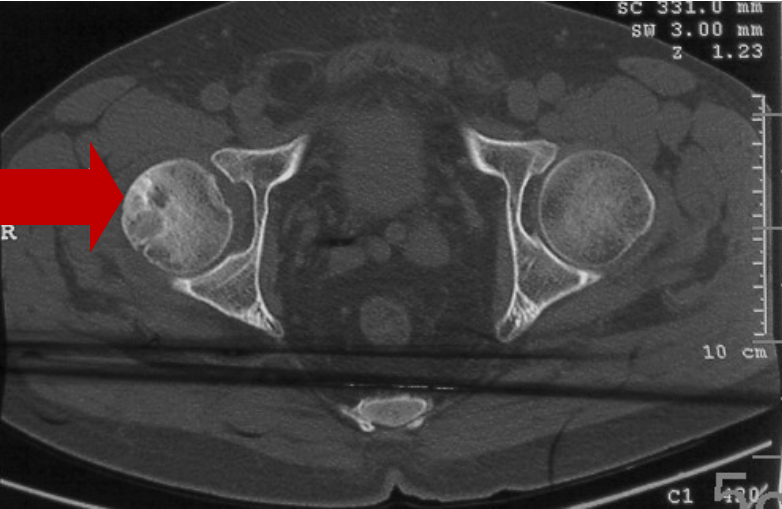

2008年10月21日CT显示:

右股骨头坏死二期

2021年05月20日末次复查CT显示:

右股骨头坏死三期,左股骨头正常